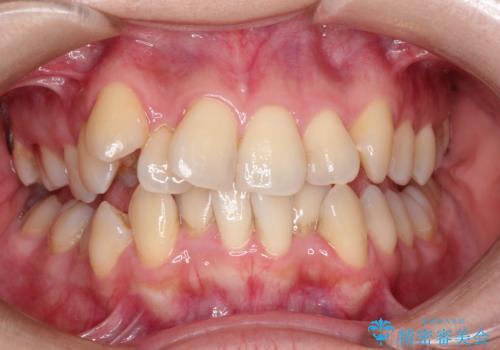

- 治療計画

- マウスピースによる矯正治療をご希望された方です。歯のガタつきが大きかったため、ワイヤーによる抜歯矯正をご提案しました。どうしてもマウスピースが良いとの強いご希望があったため、治療の途中でワイヤー治療に切り替える可能性もあることを十分ご理解いただいた上でインビザラインによる抜歯矯正治療を行いました。

1日20時間以上、正しくインビザラインを使用して頂いたおかげで、ワイヤーに切り替えることなく矯正治療を終了することが出来ました。周囲からも歯並びがすごく綺麗になったと言われたのことで大変ご満足いただけました。